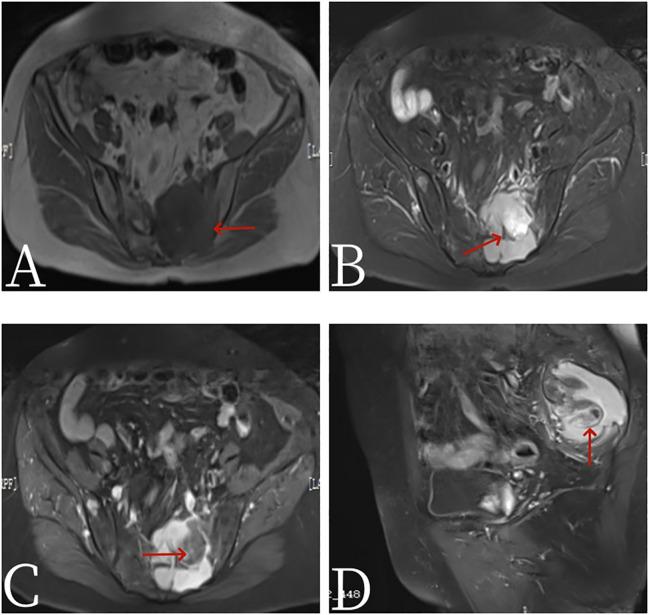

A 67-year-old female patient presented with sacrococcygeal pain without obvious causes on 16 September 2022, with occasional pain at night, as well as aggravated pain during hip flexion and long-distance walking, which could be slightly relieved with rest, without special treatment. For further treatment before 1 month to Jiangxi Provincial People's Hospital, after admission, laboratory tests were negative. Non-contrast CT scan showed expansive bone destruction in the S1-3 vertebrae with soft tissue density of about 58 mm × 46 mm × 52 mm. The boundary was clear, necrosis was visible within the vertebrae, and the boundary between the mass and the anterior sacral blood vessels and rectum was unclear. Non-contrast MRI scan showed mixed signals in lumbosacral masses, with equal signals in T1 and uneven and slightly higher signals in T2. Cystic degeneration and necrosis were visible, with multiple compartments in the lumbosacral masses. MRI enhancement showed uneven enhancement of lumbosacral mass with multiple compartments and no enhanced cystic lesion. The left sacral alar bone is destroyed, as shown by large flaky uneven strengthening. PET/CT showed that S1-3 vertebral body and left sacral alar bone were destroyed and soft tissue shadow formed, invading the sacral canal and the left foramina of S1-3. FDG metabolism was significantly increased, and malignant tumor was diagnosed by PET/CT. Pathological examination: The pathological diagnosis was monophasic PSSS. After systemic chemotherapy and local radiotherapy, no significant signs of recurrence and metastasis were found on CT so far. Follow-up treatment was continued.

2022年9月16日,一名67岁女性患者无明显诱因出现骶尾部疼痛,夜间偶有疼痛,髋关节屈曲及长途行走时疼痛加重,休息后可稍缓解,未进行特殊治疗。1个月前到江西省人民医院进一步诊治,入院后实验室检查均为阴性。非增强CT扫描显示S1-3椎体骨质呈膨胀性破坏,软组织密度影大小约为58 mm×46 mm×52 mm,边界清晰,椎体内可见坏死,肿块与骶前血管及直肠分界不清。非增强MRI扫描显示腰骶部肿块呈混杂信号,T1WI呈等信号,T2WI呈不均匀稍高信号,可见囊变坏死,腰骶部肿块呈多房性。MRI增强扫描显示腰骶部多房性肿块强化不均匀,囊变区无强化。左侧骶骨翼骨质破坏,呈大片状不均匀强化。PET/CT显示S1-3椎体及左侧骶骨翼骨质破坏并形成软组织影,侵犯骶管及左侧S1-3椎间孔,FDG代谢明显增高,PET/CT诊断为恶性肿瘤。病理检查:病理诊断为单相型PSSS。经全身化疗及局部放疗后,目前CT检查未见明显复发及转移征象,继续随访治疗。